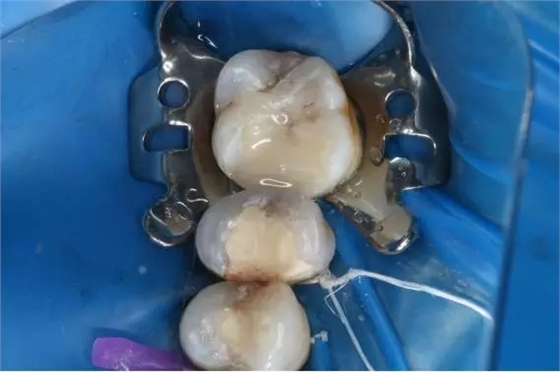

1.去除食物殘渣及大部分腐質(zhì)

2.去凈腐質(zhì)后近髓狀態(tài)